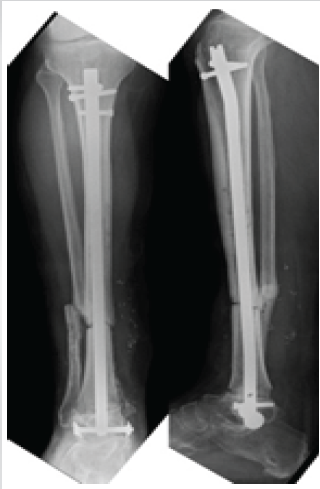

We opted for an anterograde tibiotalar intramedullary nailing with a conventional tibial nail, ensuring tibiotalar arthrodesis with stable static fixation at proximal tibial and talar level (Fig. 5).

Figure 5: Post-operative X-ray, distal tibia allograft, and anterograde tibia–talus intramedullary nailing

Resection of the infection, appropriate antibiotic therapy over a sufficient period of time, and the stability of the reconstruction have enabled the patient to gradually gain in comfort and autonomy. The current fellow-up is 9 years (Fig. 7).

Figure 7: Post-operative X-ray at 9 years fellow-up.